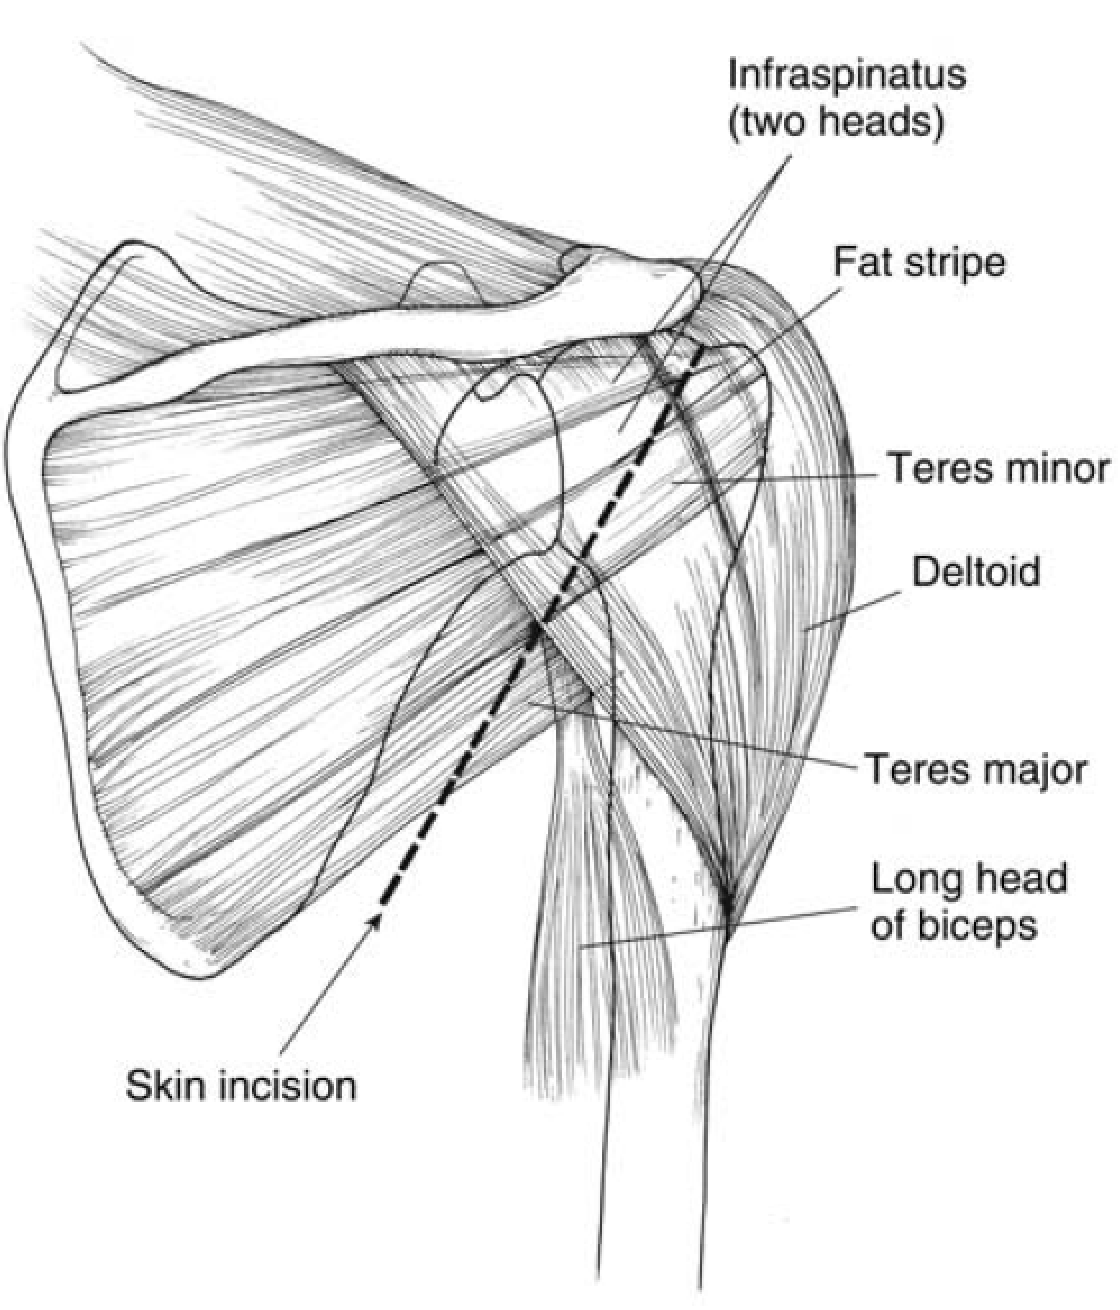

Judet Approach Shoulder

Interval: Teres Minor (Axillary n.) and Infraspinatus (Suprascapular N.)

Approach: Split deltoid or elevate from scapular spine. Fat stripe between teres minor and infraspinatus. Brings you down on capsule.

Dangers: Axillary n & post humeral circunflex a. in quadrilateral space. Suprascapular n. (3cm medial to glenoid at suprascapular notch, and 2cm medial to glenoid at spinoglenoid notch)